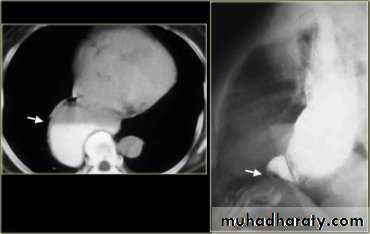

LEFT: Dilated esophagus (arrows) appears as long, well-defined structure paralleling heart RIGHT: Dilated esophagus usually deviates to right. Narrowing (arrow) at hiatus.

LEFT: CT shows dilated esophagus (arrow) that led to esophagram.RIGHT: Esophagram shows narrowing (arrow) at level of hiatus.